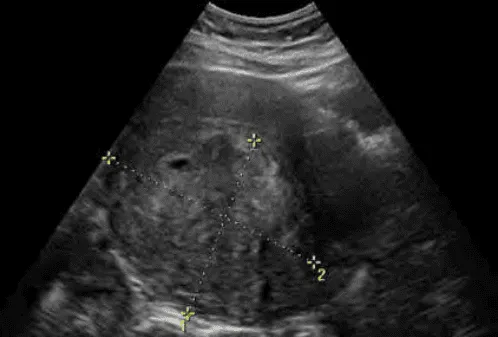

Hình ảnh “Leiomyosarcoma trên siêu âm”.